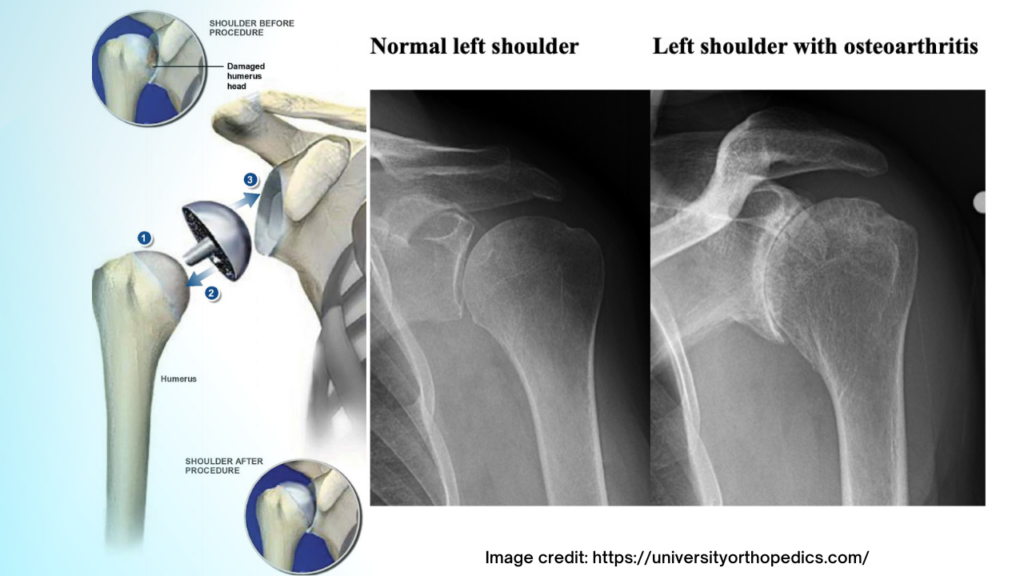

What is a shoulder resurfacing procedure?

A shoulder resurfacing procedure in orthopedics is a surgical technique designed to treat certain shoulder conditions, primarily arthritis, by preserving as much healthy bone and tissue as possible while addressing the damaged surfaces of the shoulder joint. This procedure is often considered an alternative to total shoulder replacement, particularly for younger patients or those with less severe joint degeneration.